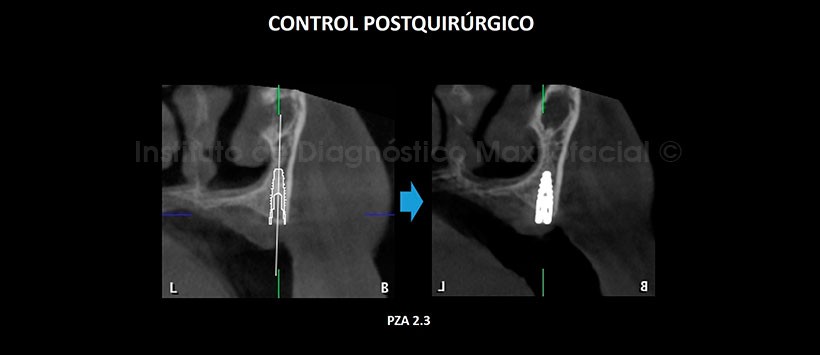

En la tomografía computarizada de haz cónico (TCHC), se realiza la planificación virtual de colocación de cuatro implantes dentales en zonas de piezas 17, 23, 26 y 27 (Figura 2, 3), y sobre la planificación se realiza la confección virtual de la guía quirúrgica (Figura 4). En la reconstrucción 3D (Figuras 5) se aprecia con detalle la orientación y la disposición final de los implantes dentales a ser colocados, además se observa la guía quirúrgica confeccionada virtualmente que posteriormente fue impresa físicamente para su utilización en el procedimiento quirúrgico (Figura 6).

En la tomografía de control post quirúrgico (Figura 7, 8, 9, 10 y 11), se aprecia los implantes con estructura ósea circundante, en las posiciones donde fueron planificadas virtualmente.